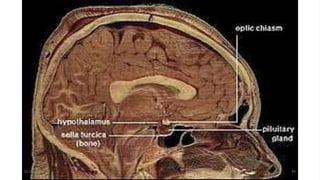

•The hypothalamus is located anterior and

inferior to the thalamus. The

hypothalamus lies immediately beneath

and lateral to the lower portion of the

wall of the third ventricle.

01-09-2020 29

•It includes the optic chiasm (the point at which

the two optic tracts cross) and the mamillary

01-09-2020 30

emotional response

bodies (involved in olfactory

to

reflexes and

odors). The

infundibulum of the hypothalamus connects

it to the posterior pituitary gland.